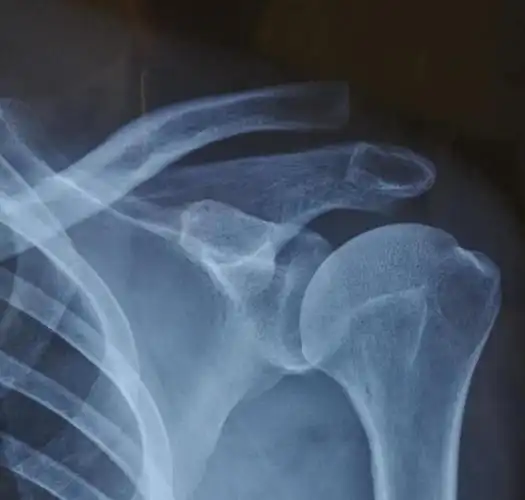

司法鉴定科学研究院对肩锁关节脱位人体损伤程度的法医临床鉴定案